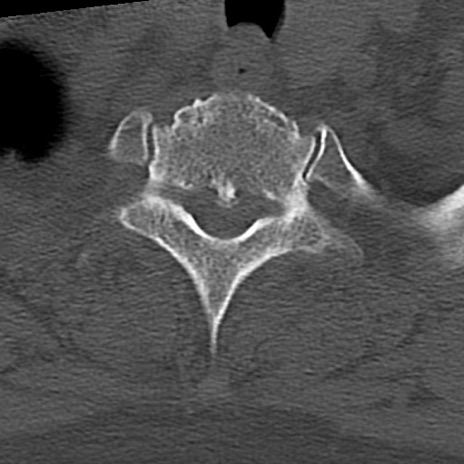

頚椎CT

横断像